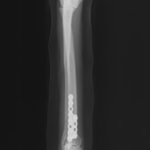

交通事故直後、胸腰部に激しい疼痛、両後肢に完全麻痺を認め、シェフシェリントン徴候を呈していました。レントゲン検査において、第11-12胸椎間の脱臼が認められました。

脊髄の減圧、脊柱管の再構築・安定化を目的に、片側椎弓切除術およびMatrixMANDIBLE Plateによる椎体固定を実施しました。

隣接椎体を架橋するようにプレートを設置しました。

術後レントゲン写真

症例:交通事故による椎体脱臼

柴犬:9歳、避妊雌